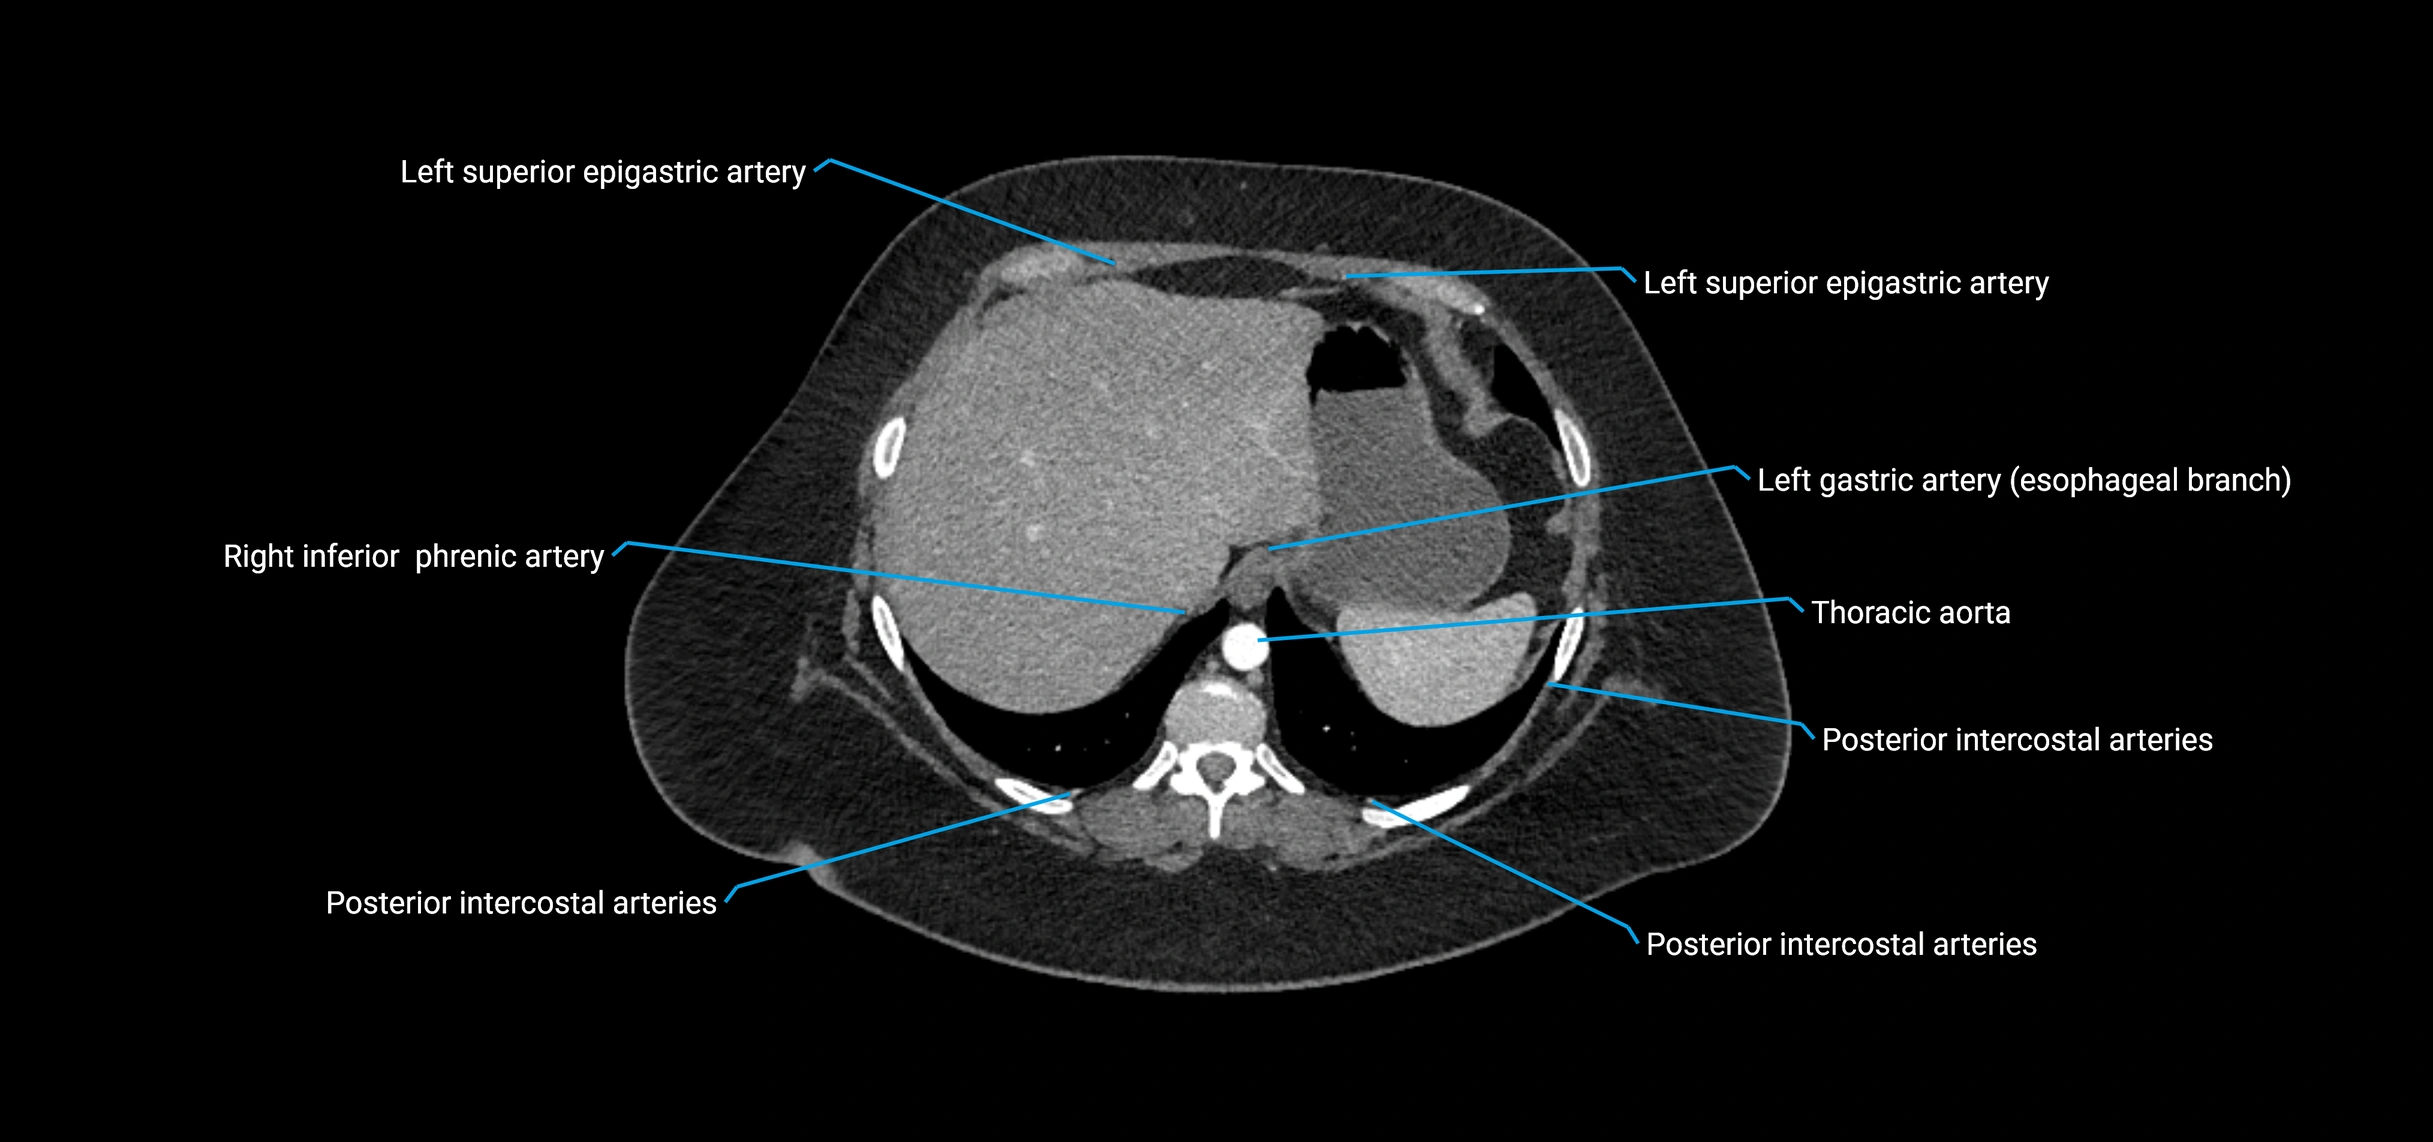

Contrast-enhanced CT (CTA):

• Gold standard for abdominal aortic imaging

• Provides excellent detail of lumen, wall, aneurysm, thrombus, and branch vessels

• Multiplanar and 3D reconstructions help in aneurysm measurement, stent graft planning, and dissection evaluation

• Detects acute rupture, traumatic injury, or occlusion with high sensitivity